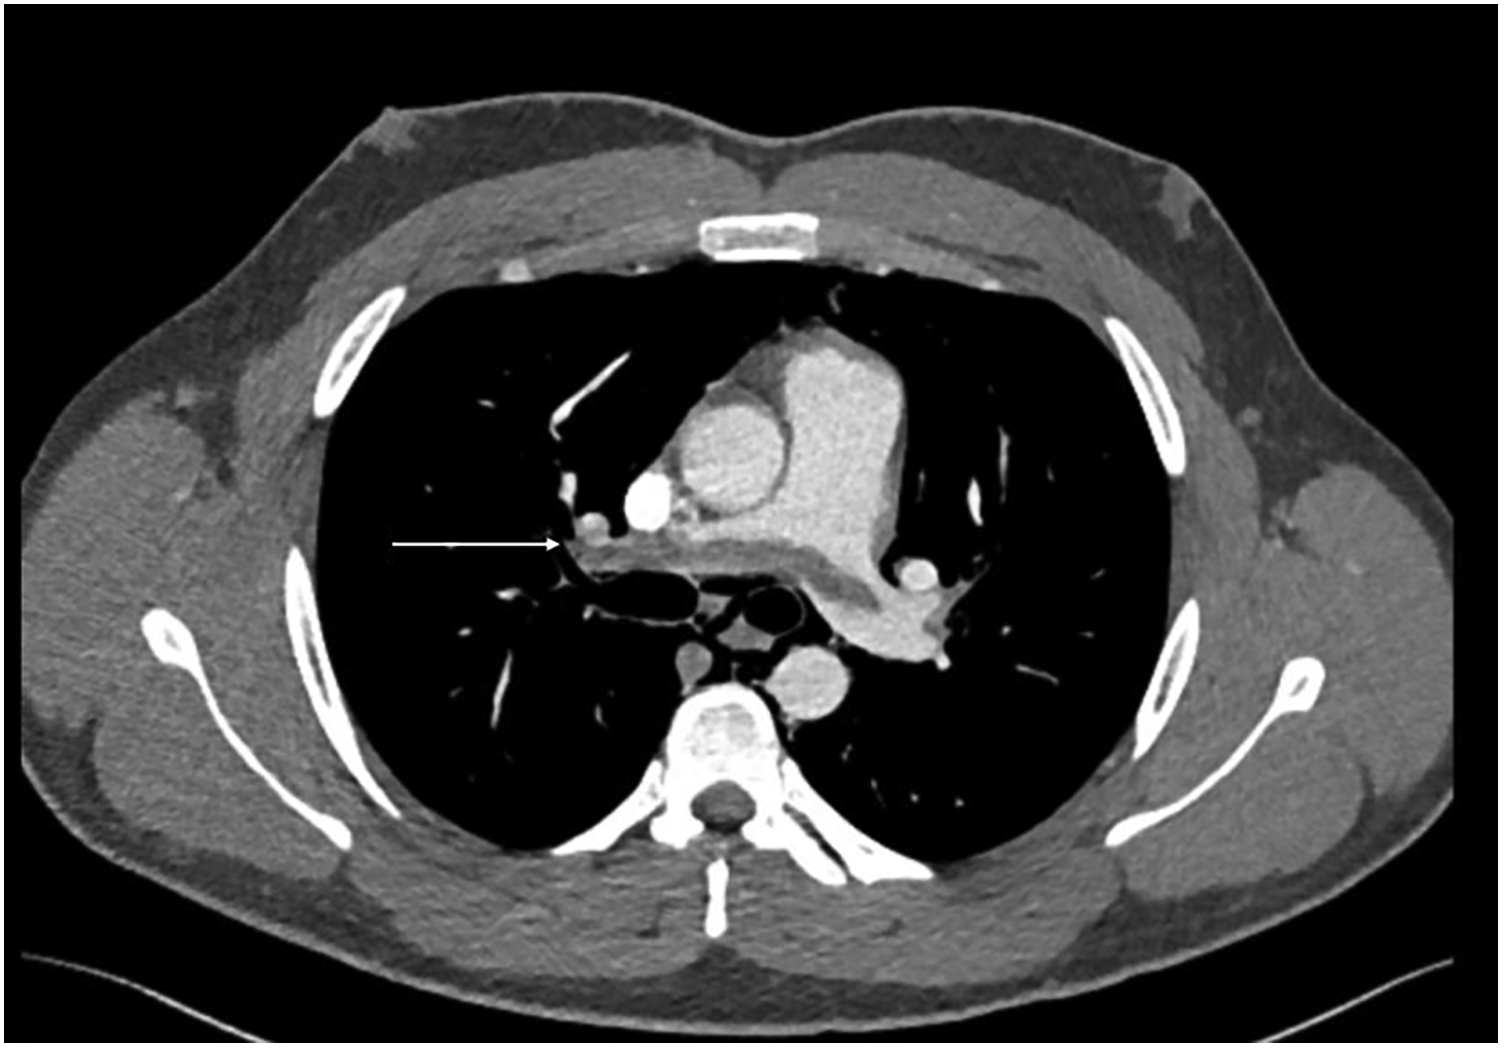

During acute coronary syndrome (ACS) exclusion workouts, transthoracic echocardiography images were very difficult to obtain, as hyperechoic moving artifacts were interfering with the ultrasound probe. Immediate chest x-ray showed massive pneumomediastinum (Figure 1). A subsequent CT scan confirmed the massive pneumomediastinum (Figure 2) and revealed the presence of an acute bilateral pulmonary embolism (Figure 3). Laboratory tests showed elevated D-Dimer levels (2,515 ng/mL), polycythaemia (hemoglobin 18.9 g/dL, haematocrit 55.5%), and slightly elevated creatinine (1.48 mg/dL, creatinine clearance 49 mL/min) with mild hypoalbuminemia (3.2 g/dL).

Figure 3

CT scan—CTPA demonstrates saddle pulmonary embolism extending to subsegmental branches bilateral (arrow demonstrates a large thrombus extending across the pulmonary artery bifurcation).